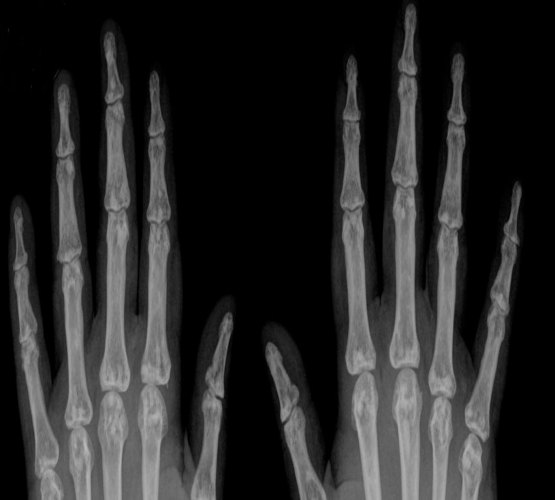

Você tem hábito de estalar os dedos? Saiba o que isto pode causar